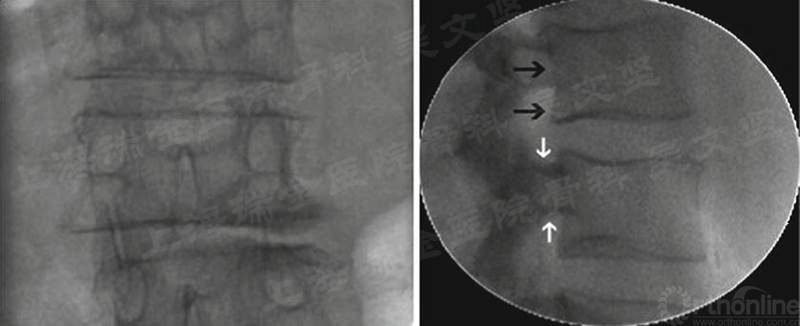

术前通过调整体位、手术床获得真正的正侧位透视。理想的正位透视,棘突应该位于中间,上下终板平行,如果患者有脊柱侧弯,建议通过调整手术床而不是通过调整C臂获得真正的正位透视。理想的侧位透视,椎体上下终板应该平行,椎弓根上下缘清晰无重叠影。(图1)

图1 理想的正侧位透视